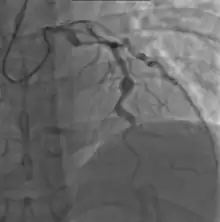

Angiography showing ectatic LAD, with largest aneurysm = 6.5 mm in diameter

Since no specific laboratory test exists for Kawasaki disease, diagnosis must be based on clinical signs and symptoms, together with laboratory findings.[9] Timely diagnosis requires careful history-taking and thorough physical examination.[119] Establishing the diagnosis is difficult, especially early in the course of the illness, and frequently children are not diagnosed until they have seen several health-care providers. Many other serious illnesses can cause similar symptoms, and must be considered in the differential diagnosis, including scarlet fever, toxic shock syndrome, juvenile idiopathic arthritis, and childhood mercury poisoning (infantile acrodynia).[120]